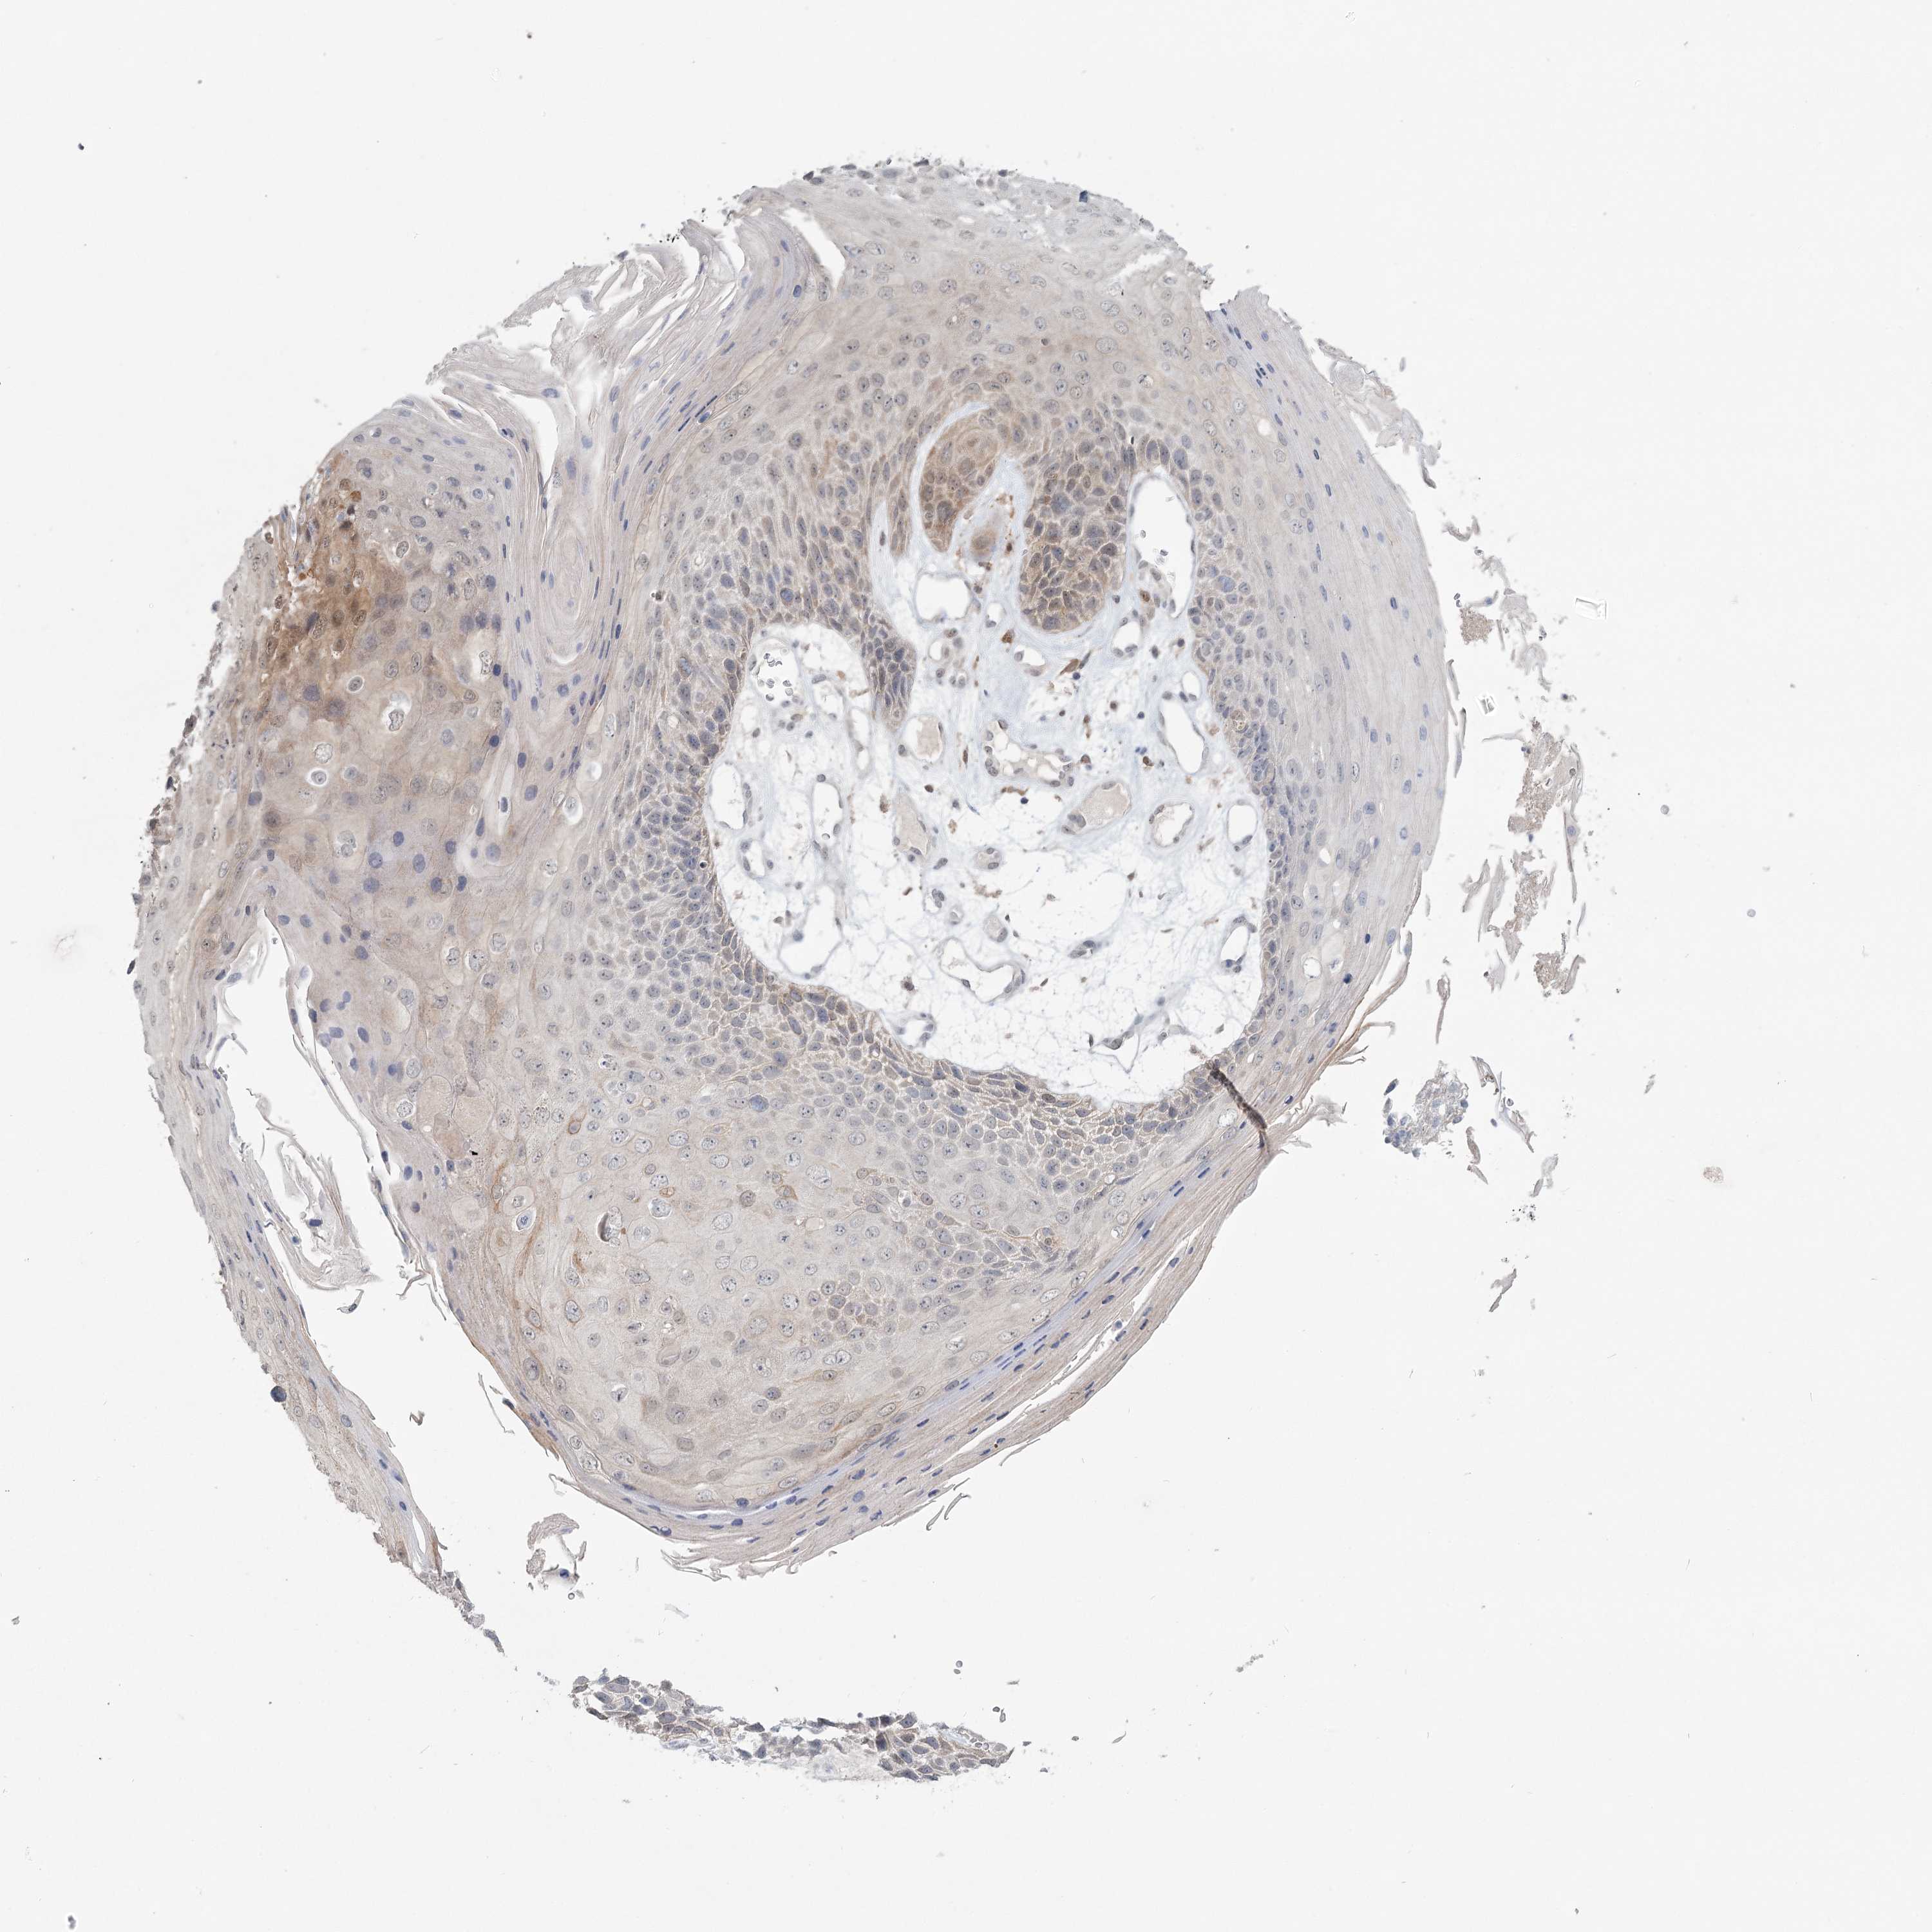

Basal cell and squamous cell cancer

SKIN CANCER - Protein expressioni

A mouse-over function shows sample information and annotation data. Click on an image to view it in a full screen mode. Samples can be filtered based on level of antibody staining by selecting one or several of the following categories: high, medium, low and not detected. The assay and annotation is described here.

Antibody stainingi

Antibody staining in the annotated cell types in the current human tissue is reported as not detected, low, medium, or high, based on conventional immunohistochemistry profiling in selected tissues. This score is based on the combination of the staining intensity and fraction of stained cells.

Each image is clickable and will lead to virtual microscopy that enables deeper exploration of all samples and also displays staining intensity scores, fraction scores and subcellular localization as well as patient and tissue information for each sample.

Antibody HPA023187

Antibody CAB034226

Staining

High

Medium

Low

Not detected

Intensity

Strong

Moderate

Weak

Negative

Quantity

>75%

75%-25%

<25%

None

Location

Nuclear

Cytoplasmic/membranous

Cytoplasmic/membranous,nuclear

Basal cell carcinoma